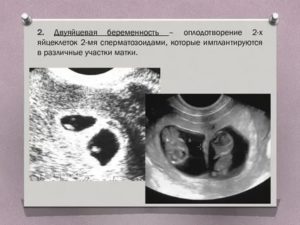

Механизм зачатия однояйцевой и двуяйцевой двойни существенно отличается. Формирование двуяйцевой беременности осуществляется при синхронном оплодотворении сразу двух яйцеклеток, имплантирующийся в отдельные участки матки.

Нередки случаи формирования двуяйцевых близнецов вследствие двух различных половых актов, совершенных в течение недели. Однако возможен и один акт. Отличительной чертой двуяйцевой двойни является наличие плодного пузыря и отдельной плаценты у каждого плода.